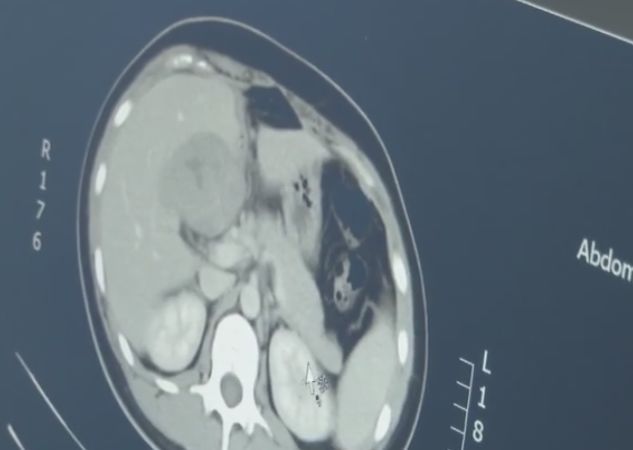

有明显的怀孕指征却找不到孕囊,医生怀疑出现了宫外孕,于是为患者做了CT检查,结果发现,这是一个罕见的宫外孕病例,胚胎跑到了肝脏部位。

据介绍,宫外孕常见于输卵管附近,胚胎跑到肝脏部位极为罕见,很容易引发大出血,危及生命。